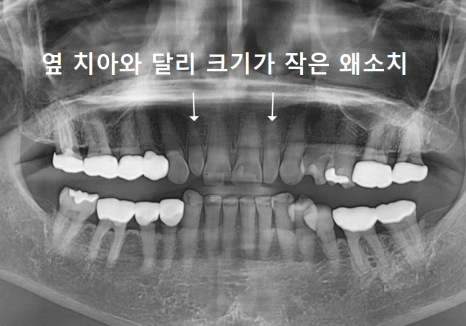

입안을 자세히 보니

앞니 사이를 메운 레진이 깨져 있었고,

그 양옆 작은 앞니가

다른 치아보다 눈에 띄게 작았습니다.

이렇게 주변 치아보다 유난히 작은 치아를

‘왜소치’라고 부릅니다.

왜소치는 크기가 작다 보니

그 주변으로 공간이 남기 쉽고,

결국 앞니 사이가 더 벌어져 보이는 원인이 됩니다.